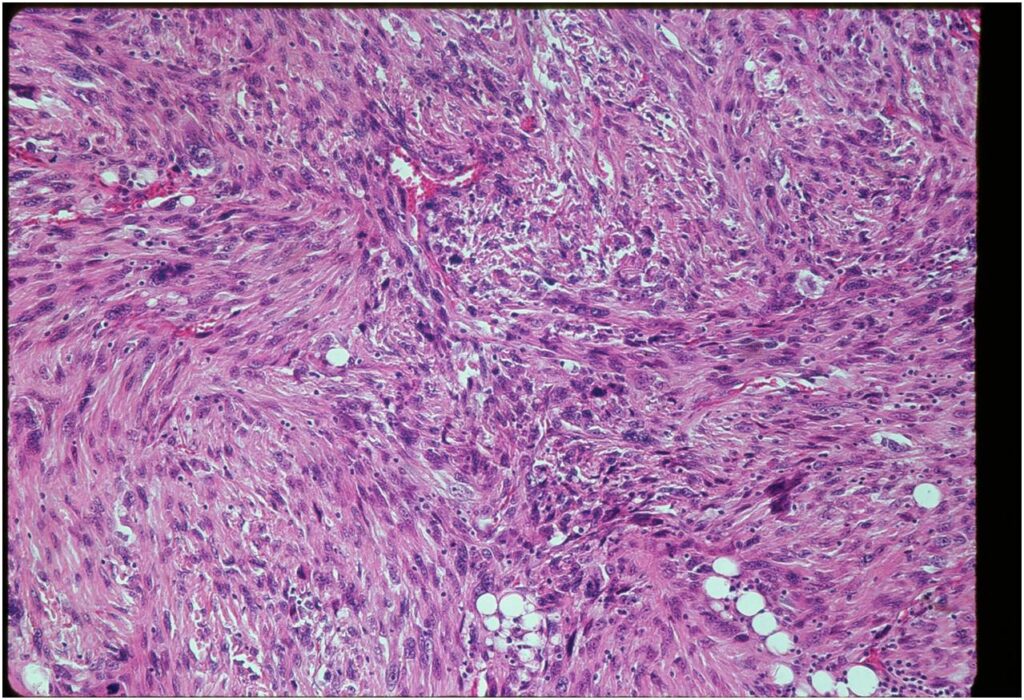

Microscopic Pathology

- Chondrosarcoma component is often grade I (Low Grade Hyaline Type Cartilage)

- Dedifferentiated component

- Predominant noncartilaginous/spindle sarcoma component varies

- Fibrosarcoma and MFH most frequently reported

- MFH is a high grade pleomorphic spindle cell tumor with a storiform pattern

- Osteosarcoma is third most common dedifferentiated component

- Rhabdomyosarcoma and angiosarcoma also reported

Junction of cartilaginous and noncartilaginous components is sharp and distinct. There are no dedifferentiated areas admixed in the middle of the cartilaginous areas